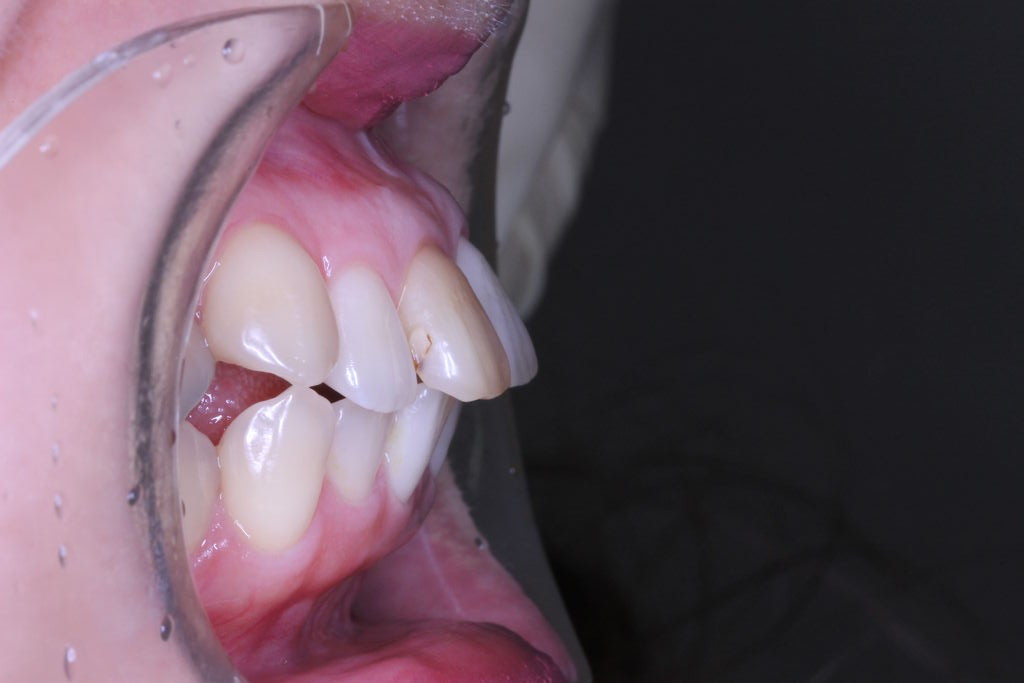

それでは本日の症例です

虫歯治療はきちんとされてますが、奥歯に全部銀歯の状態の歯があります。

当然、神経もない歯です。治療されたのはだいぶ前とのことでした。

患者さんの主訴は口元をひっこめたいでした。

そうなると抜歯しての歯列矯正治療は必須です。また、口元の改善を考えると、前歯よりの歯を抜歯したほうが治療的には容易です。

しかしながら、いつ治療したか記憶にない銀歯があります。神経もとってしまってますし、中がどのような状態になっているか把握できません。治療中に歯がとれてしまい、結果的に抜歯となってしまう可能性もございます。

結論としては、治療期間が長くかかってもかまわないので、銀歯を抜いて矯正治療をしたいとのことでした。

それでは治療経過です

少し経過が進みました

治療開始から3年経過した現在の状況です

もともとは

上の歯列はどうでしょうか?